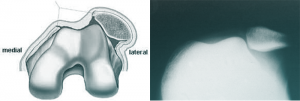

• Dysplasie de la trochlée : C’est la cause la plus fréquente. La gorge du fémur (trochlée) est trop plate, voire bombée, au lieu d’être creusée. Elle ne peut donc plus retenir efficacement la rotule, qui a tendance à glisser sur le côté.